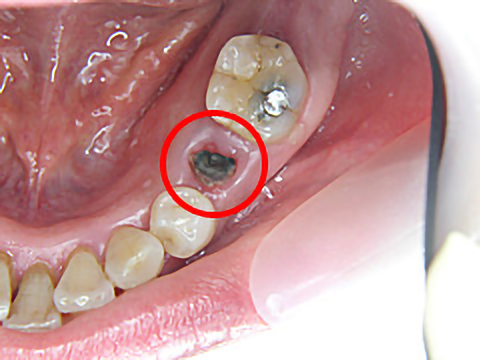

虫歯が進行して被せ物が取れてしまったため、当院にて「抜歯即時埋入」という方式のインプラント治療を選択されました。

抜歯した当日にインプラント治療を行うことで、骨がやせるのを抑えられる上、治療期間を短縮することが可能です。